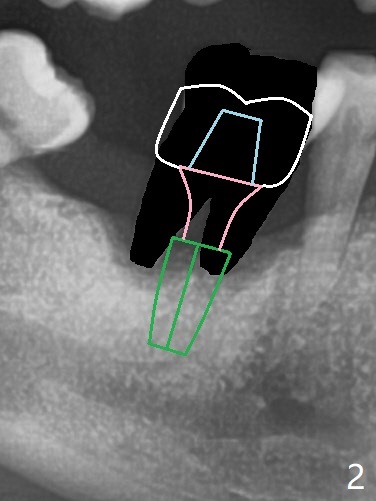

69岁男拔除左上5后右下6疼痛,要求拔除,骨质吸收严重,牙龈厚(图一:双箭头),其实后者是好事,血供好,植牙可以种植浅些(图二),周围放置骨粉(图三:红圆圈)。拍摄根尖片:近中牙槽窝种植与中隔种植,植体长度有优势(图五,四)。